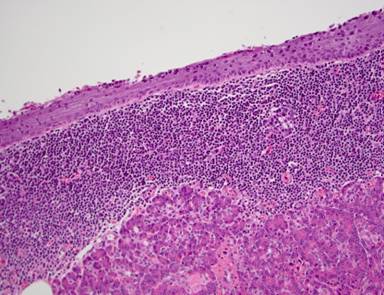

The final pathological reports in these six patients were consistent with lymphoepithelial cysts of the pancreas. The cysts were multiloculated and were lined with a well differentiated, keratinized squamous epithelium and associated with aggregates and sheets of benign lymphocytes (Figure 4). One of the cysts contained keratinaceous debris and one showed numerous small nodular projections, which protruded into the lumen.

Figure 4. Cyst wall lined by benign squamous epithelium with underlying lymphoid aggregates. Normal pancreas is present beneath this (Case #5). |